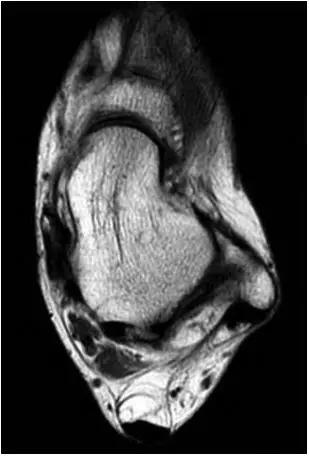

3、MR表现:

- 三角籽骨或距骨后三角结构模糊和变形,T1WI信号降低, T2WI信号升高,

- 周围脂肪水肿,

- 踇趾长屈肌腱信号升高,见鞘膜积液,

- 胫骨后下跟骨上缘骨结构形态变化和信号异常,

- 三角籽骨和距骨退行性囊变。